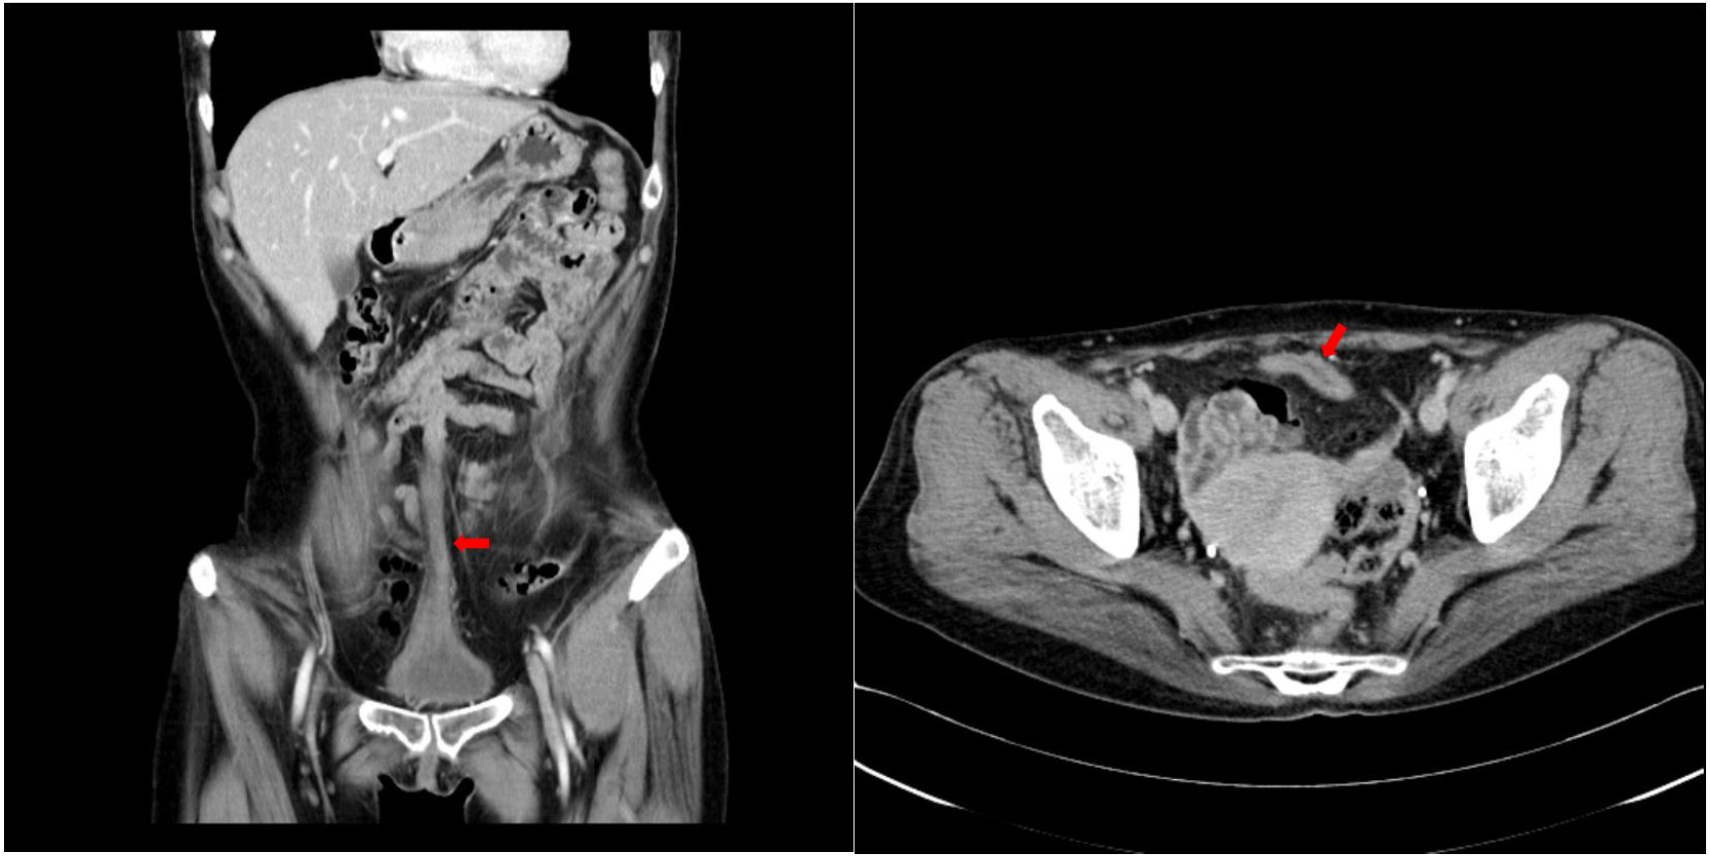

35세 여성이 몇 달 전부터 배꼽에서 소변이 나오는 것을 주 증상으로 내원하였다. 수년 전부터 시작되었다고는 하나 그때는 분비량이 매우 적어 별다른 신경을 쓰지 않고 살아왔으며, 최근 들어서 그 양이 점점 증가하였다고 하였다. 특히 성관계 시에 나오는 양이 상당히 많았으며, 소변을 참거나 배에 힘을 주면 증가한다고 하였다. 배꼽으로 소변이 나오는 것 외에 육안적 혈뇨나 배뇨통 등은동반되지 않았다고 하였다. 미혼 여성으로 출산력은 없었으며 그 밖에 과거력 상 특이사항은 없었다. 신체검사에서 배꼽은 정상적인 모양을 하고 있었으나, 방광경 검사에서 방광 전벽에 개구부가 확인되었으며 [그림 1], 양측 요관구는 정상적인 위치에 있었고, 방광내의 종물 등은 관찰되지 않았다. 내원하여 시행한 요배양 검사에서는 Streptococcus anginosus가 배양되었으며, 요세포 검사에서 이상은 발견되지 않았다. 이후 촬영한 복부 전산화 단층촬영에서 배꼽에서 방광 전벽까지 연결되는 튜브 모양의 구조물이 관찰되어 개방 요막관으로 진단하였으며 [그림 2], 주변으로 석회화나 이상 종괴는 발견되지 않았다. 항생제 경구 복용을 시작하였으며, 수술적인 치료가 계획되었다.